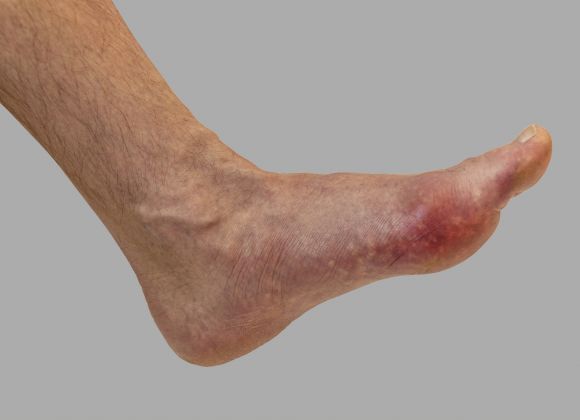

• Dna a revmatismus

Dna a revmatismus

Jeden z nejvíce patrných dopadů obezity na tělo je zvýšené opotřebení kloubů, především ve spodních končetinách. Typické jsou problémy s koleny, kotníky a kyčlemi, které jsou zvýšenou vahou vystavovány většímu tlaku, což může vést až k artróze. K problémům s klouby se může přidat také dna, způsobující velké bolesti kloubů.